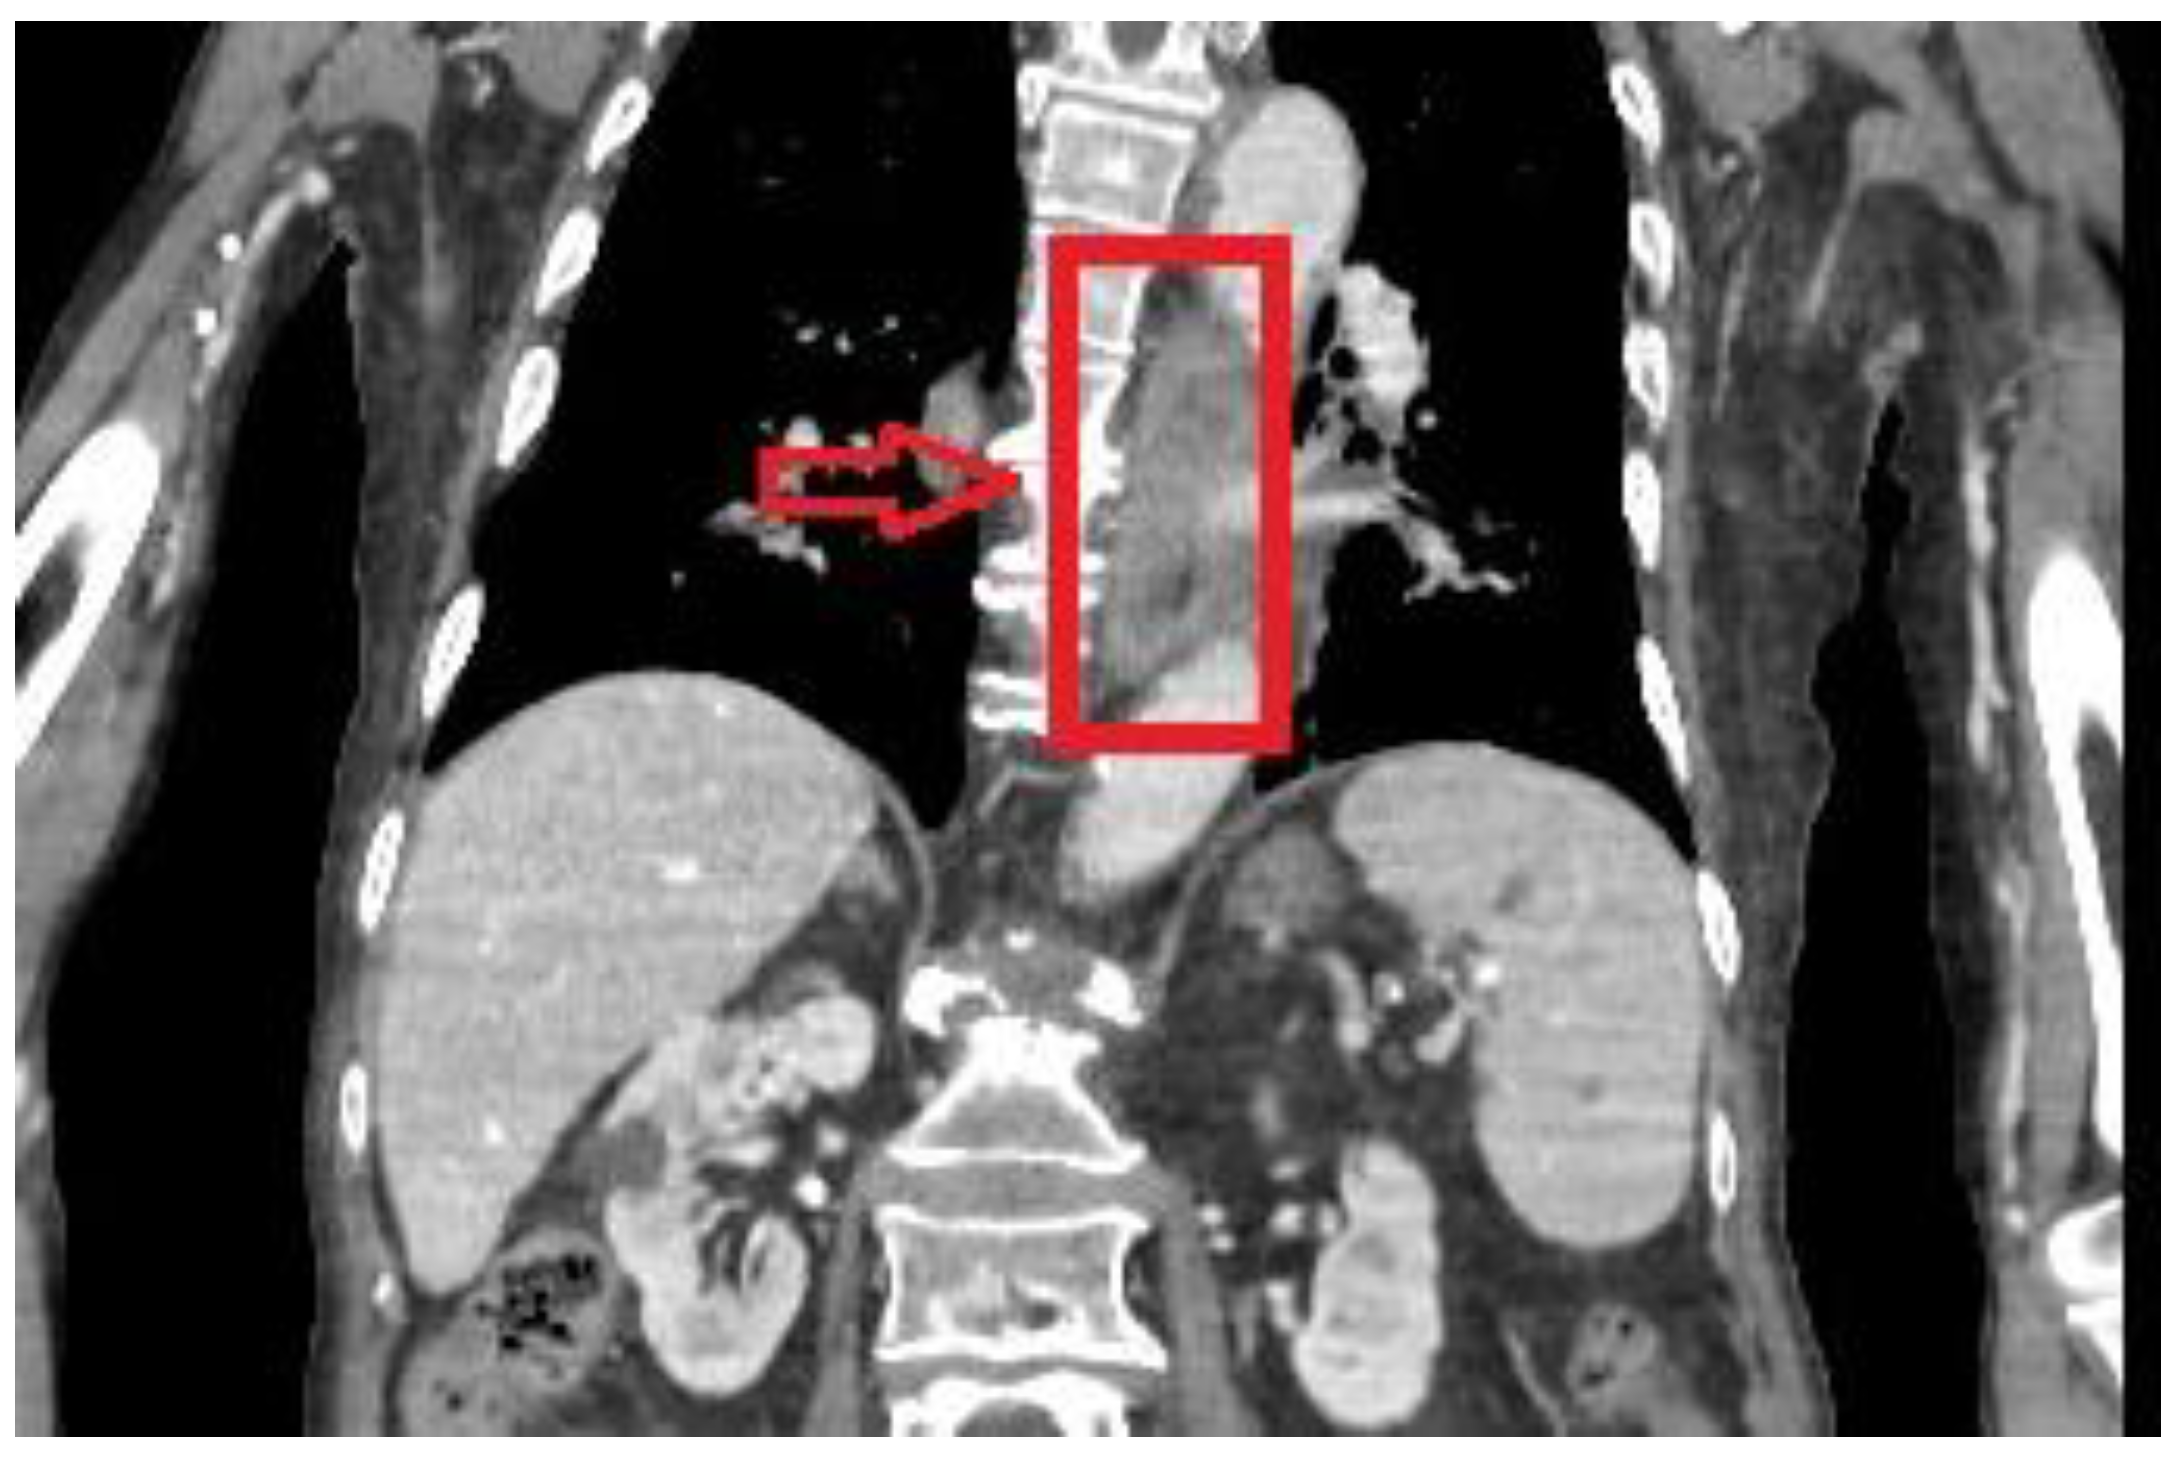

2.7. Imaging Examination